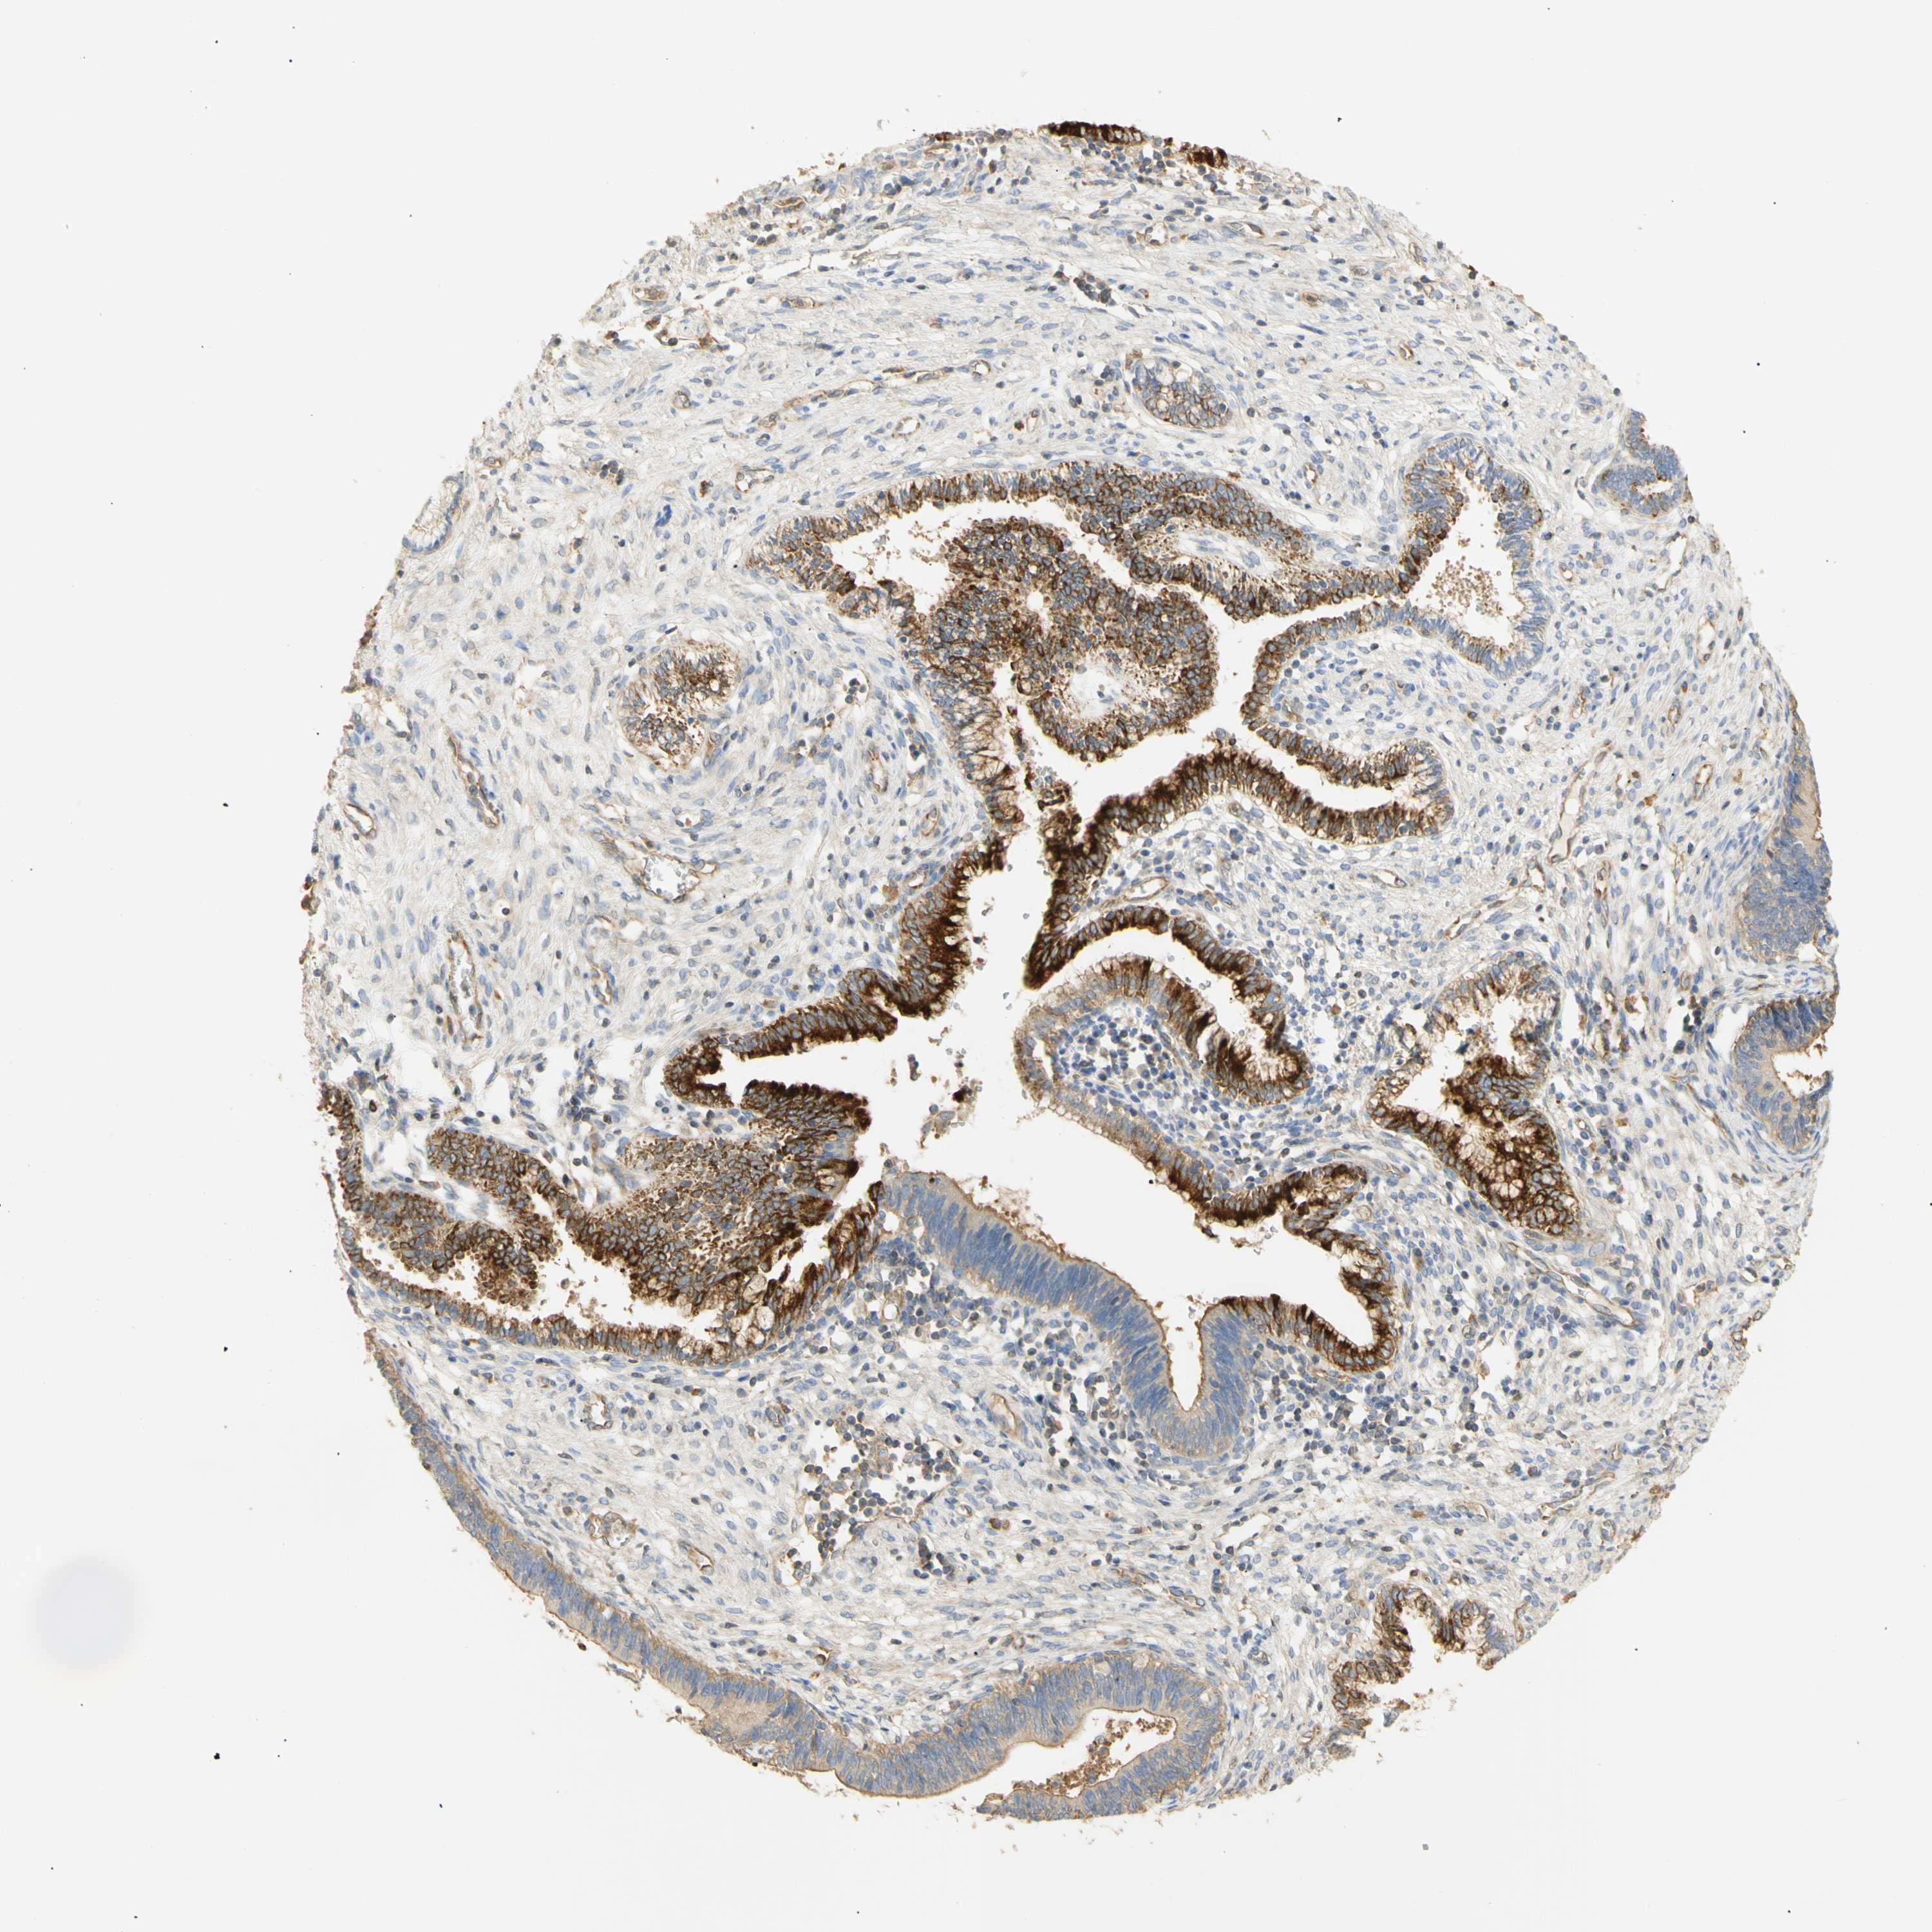

CERVICAL CANCER - Protein expressioni

A mouse-over function shows sample information and annotation data. Click on an image to view it in a full screen mode. Samples can be filtered based on level of antibody staining by selecting one or several of the following categories: high, medium, low and not detected. The assay and annotation is described here.

Note that samples used for immunohistochemistry by the Human Protein Atlas do not correspond to samples in the TCGA dataset.

Antibody stainingi

Antibody staining in the annotated cell types in the current human tissue is reported as not detected, low, medium, or high, based on conventional immunohistochemistry profiling in selected tissues. This score is based on the combination of the staining intensity and fraction of stained cells.

Each image is clickable and will lead to virtual microscopy that enables deeper exploration of all samples and also displays staining intensity scores, fraction scores and subcellular localization as well as patient and tissue information for each sample.

Antibody HPA011420

Staining

High

Medium

Low

Not detected

Intensity

Strong

Moderate

Weak

Negative

Quantity

>75%

75%-25%

<25%

None

Location

Nuclear

Cytoplasmic/membranous

Cytoplasmic/membranous,nuclear

Squamous cell carcinoma, NOS

Adenocarcinoma, NOS